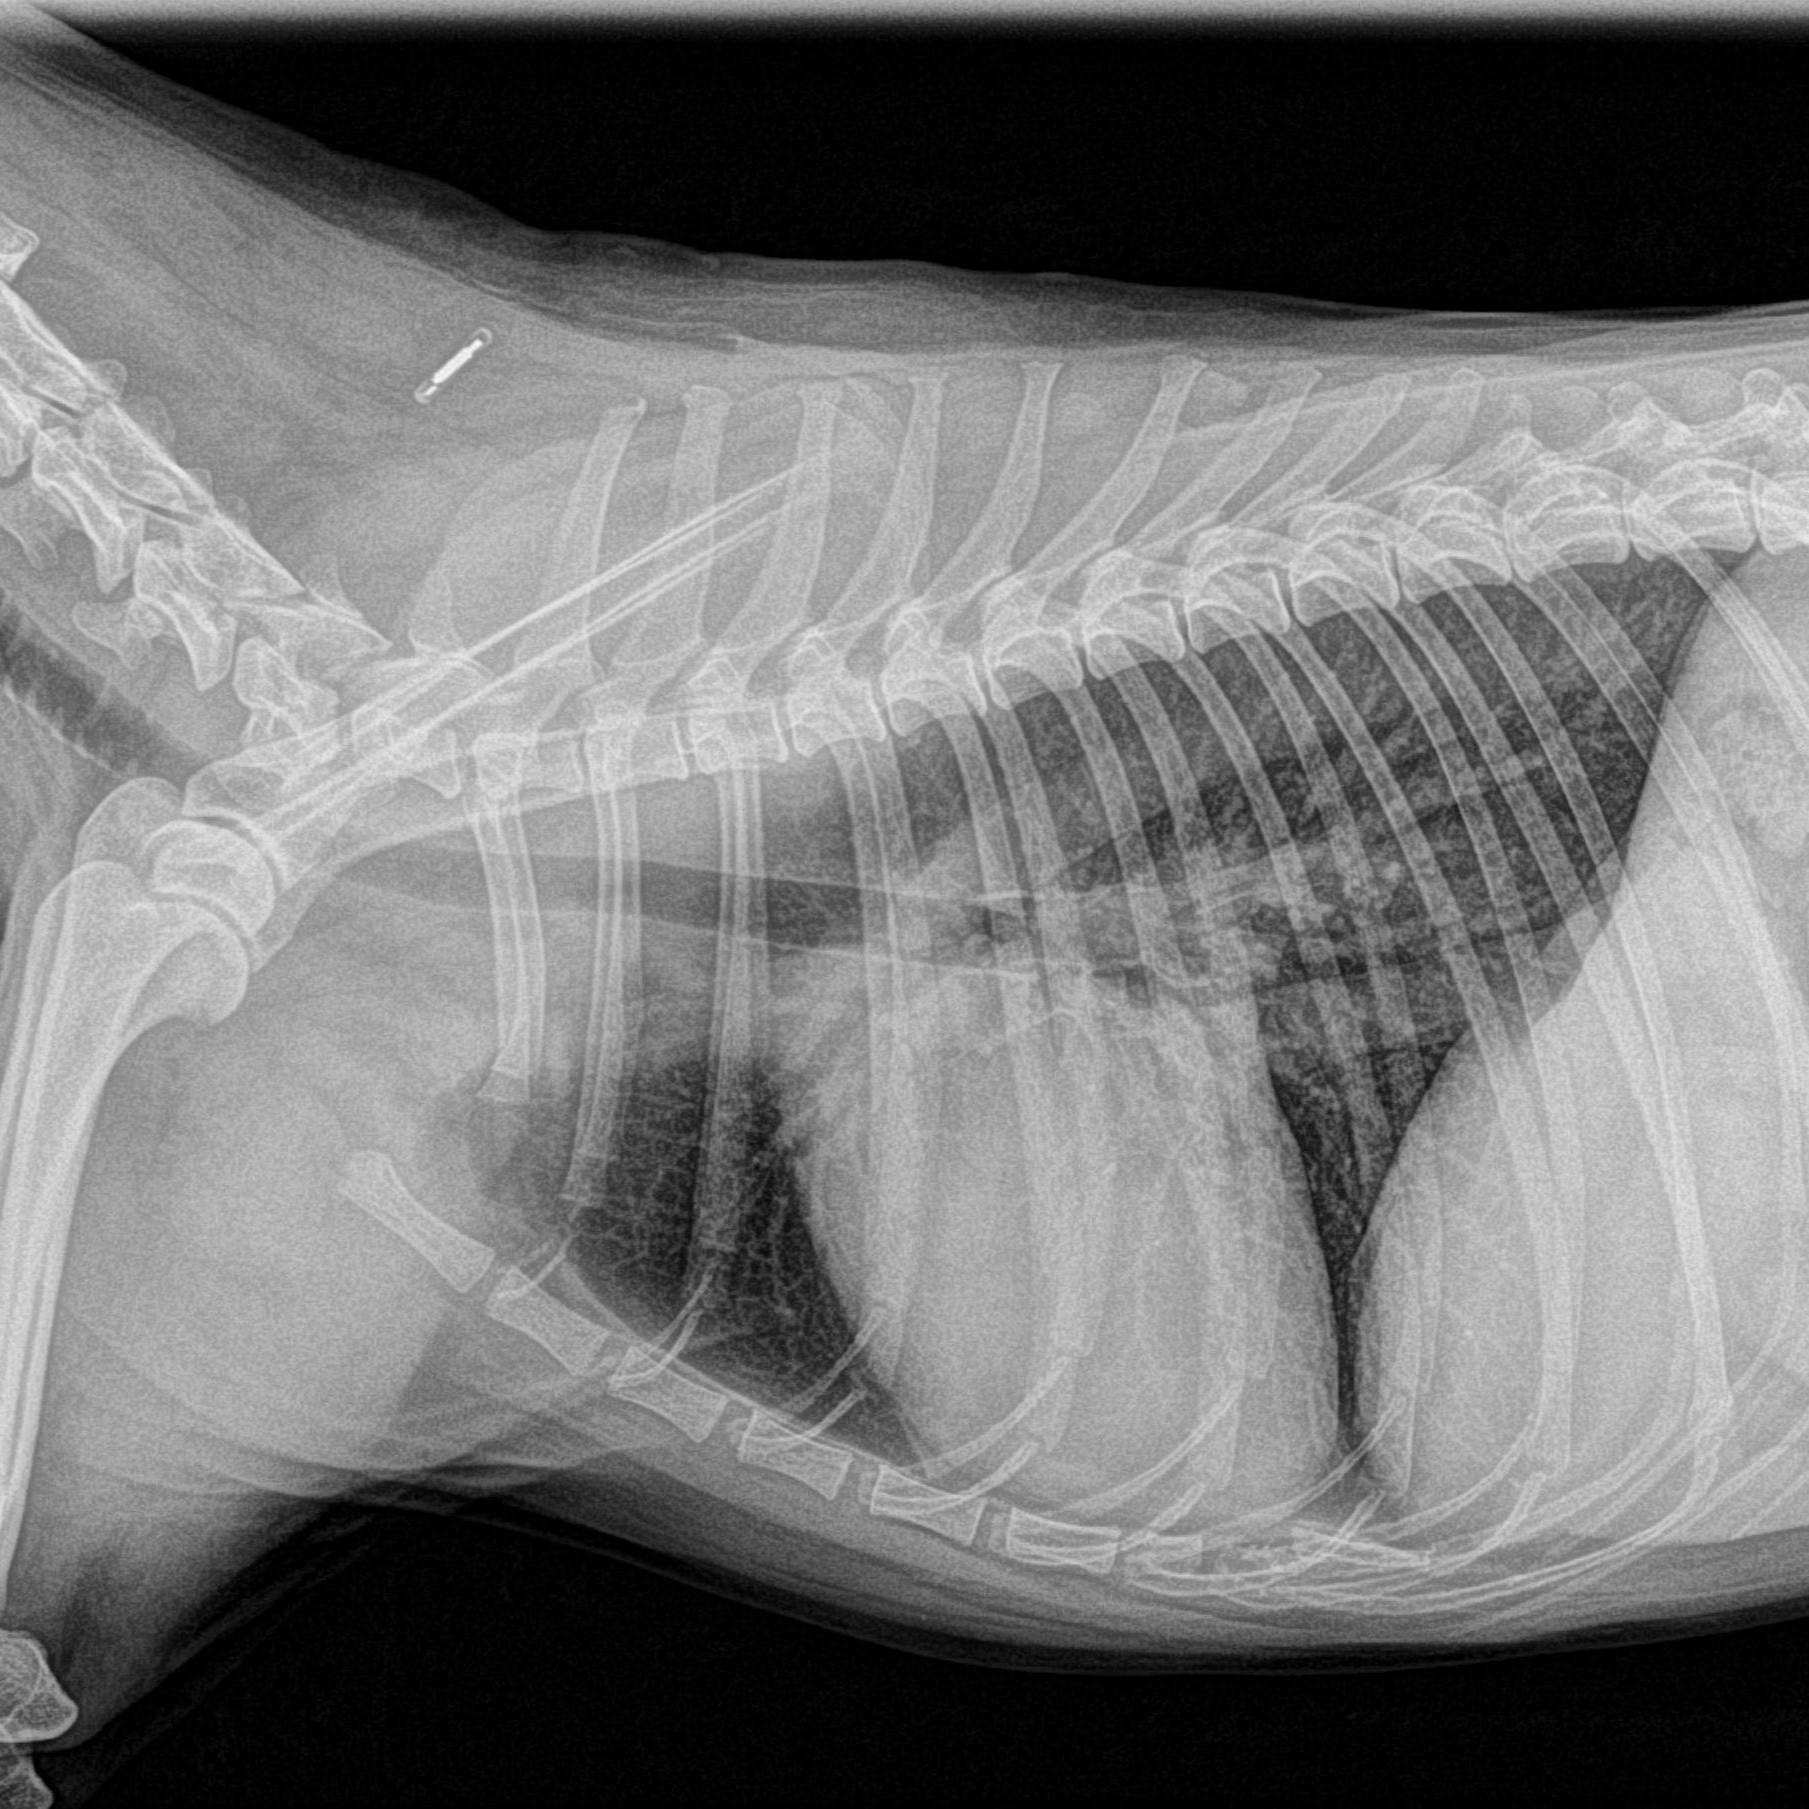

Radiographie thoracique

Elle est utilisée pour repérer d'éventuelles anomalies de la forme du cœur et pour visualiser les poumons. Lors d'un processus cancéreux, elle permet également la recherche de métastases pulmonaires.

thorax de chien